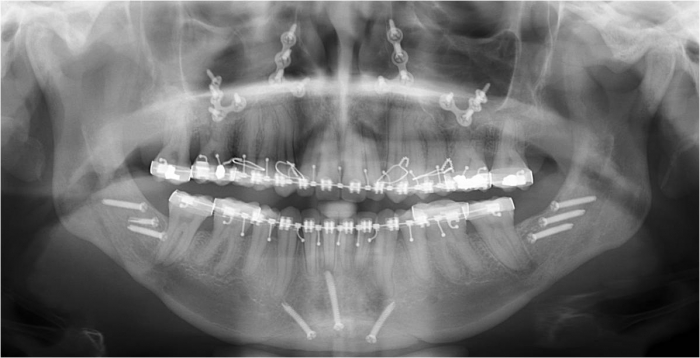

Raio x inicial